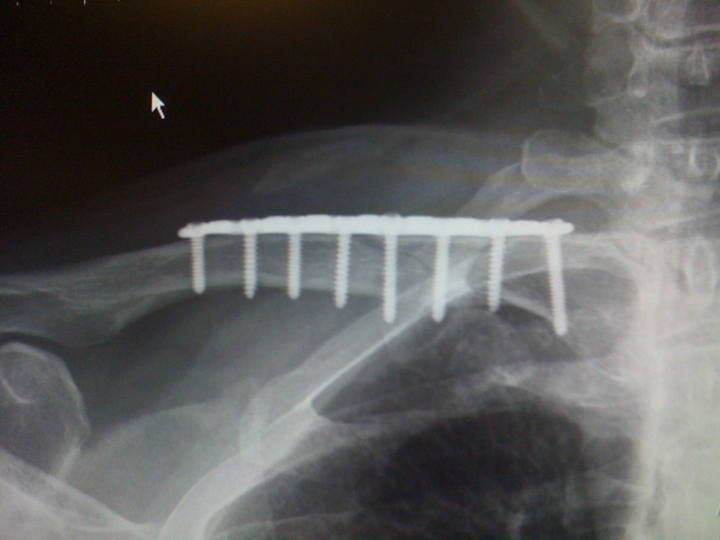

Under the expert hands of Dr. Andrew Bulczynski my injury is on the mend. The surgery took 1 hour at our D.I.S.C. facility in Marina del Rey, California. I was also incredibly fortune to also have World renown surgeon, head of D.I.S.C. and good friend Dr. Robert Bray assisting on the operation. I was in good hands to say the least! I had my surgery on September 24 and now a month later I feel like I’m ready to race again! But it’s still only been four weeks out from the surgery and my bones need 6-8 weeks to truly fuse back together.